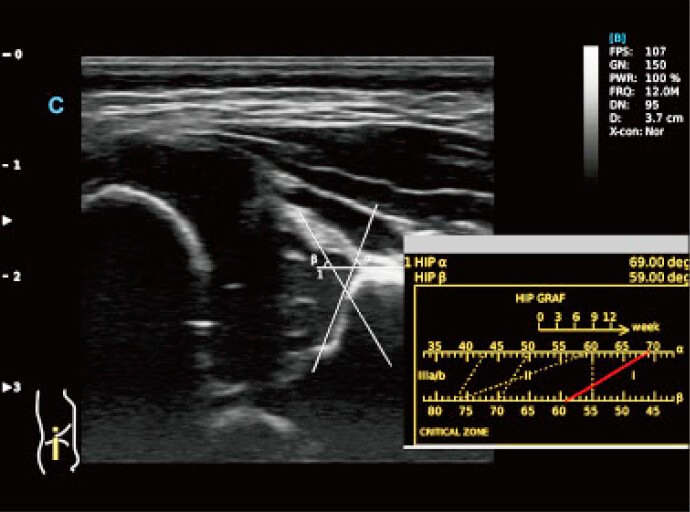

Fonction Smart Hip

- Utilisez le graphique pour diagnostiquer une orthèse de hanche.

- Différents angles indiquaient différents niveaux de déformation de la hanche, ce qui est plus facile et plus évident à voir à l'aide de ce tableau. (I, II, D, IIIa, IIIb)